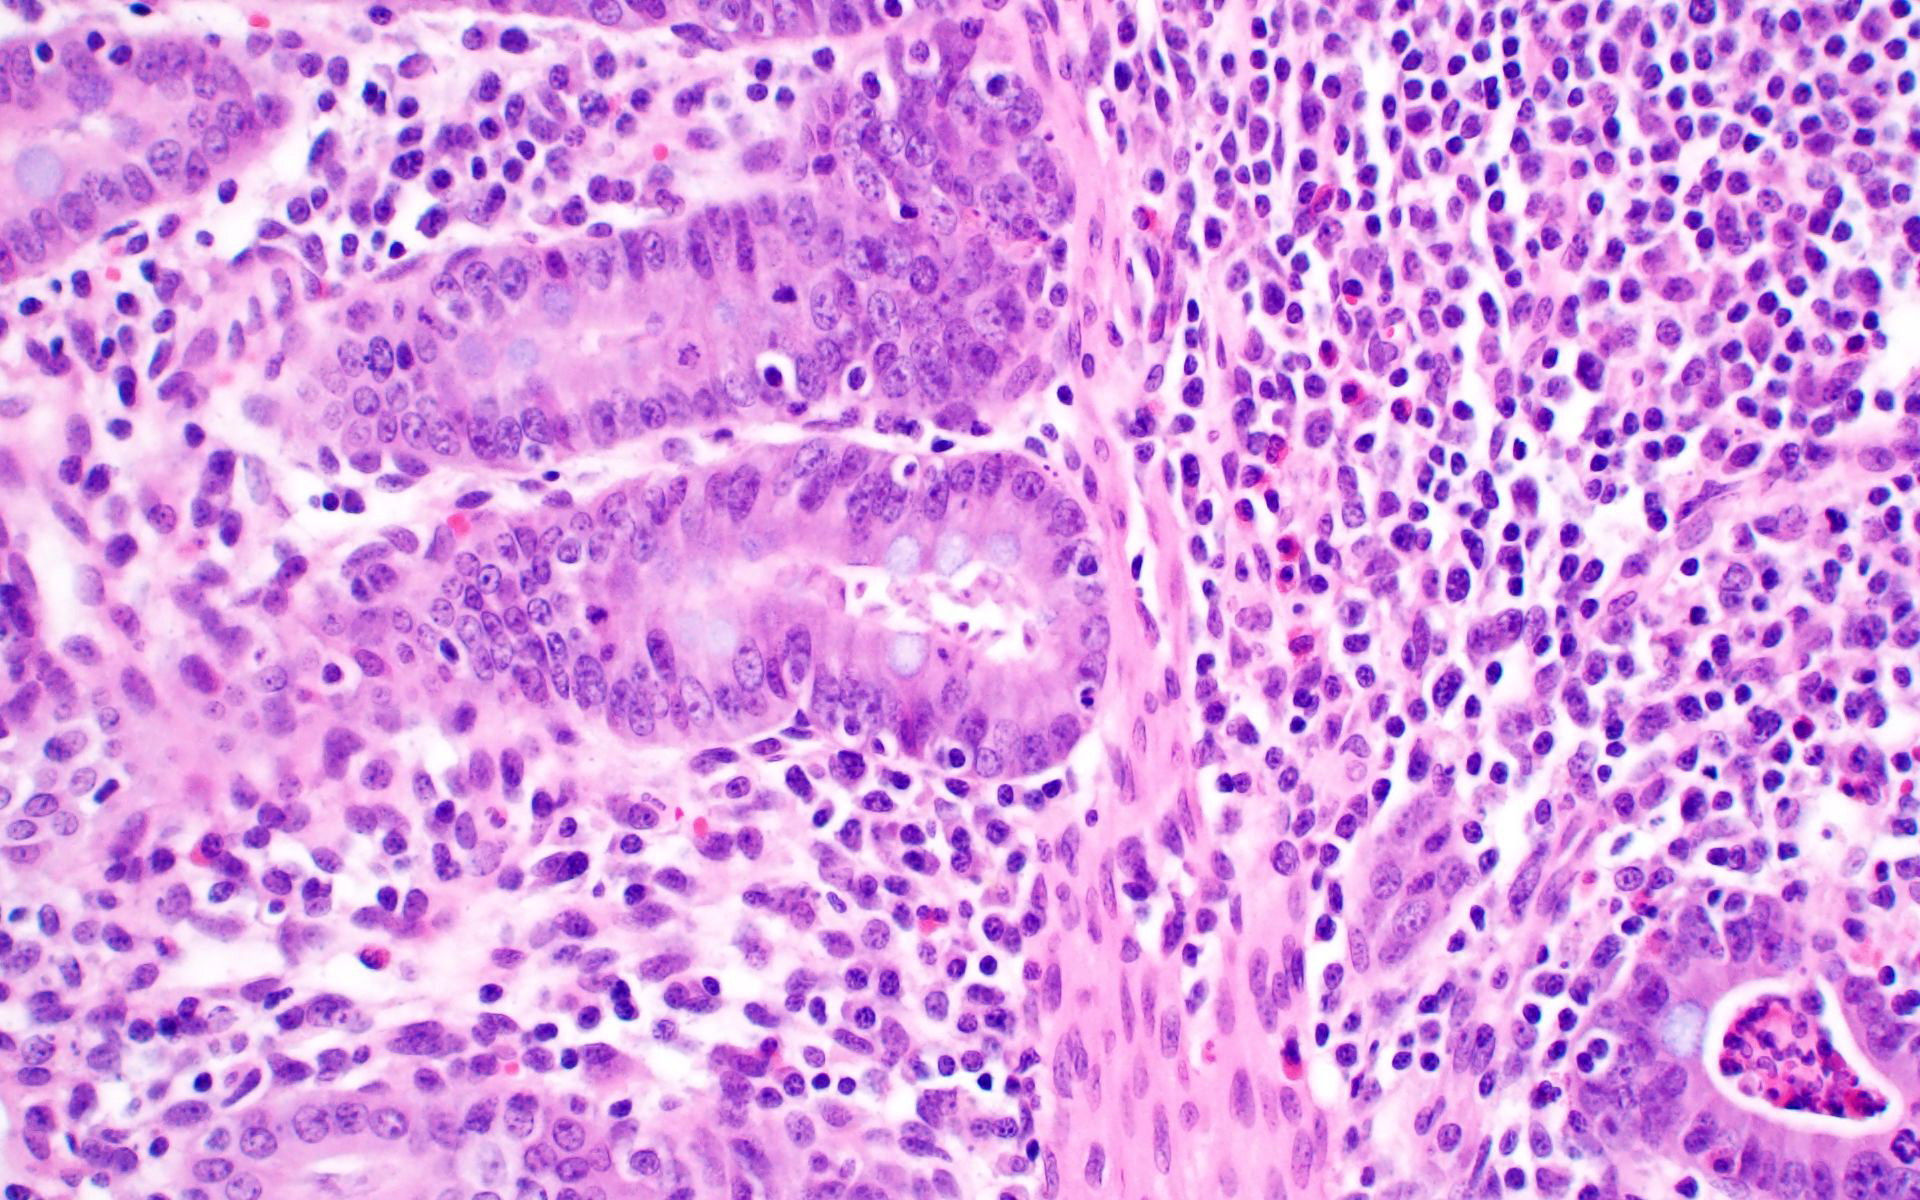

Ileum: In several sections, there is moderate multifocal blunting and fusion of villi with a crypt: villus ratio of 1:1. Apical enterocytes are often moderately attenuated with loss of the brush border and reduced apical cytoplasm. In some sections, these cells have a profound number of intracellular but extracytoplasmic 1-2 um circular eosinophilic apicomplexan organisms with 0.5 um basophilic nuclei (Cryptosporidium sp.). In other sections, these cells contain numerous larger apicomplexans with varied life-stages apparent including: 10 x 5 um curvilinear binucleate meronts (type I meronts), 4 x 12 um curvilinear uninucleate merozoites (type I merozoites), 9 x 6 um ovoid multinucleate meronts (type II meronts), multiple 3 x 12 um curvilinear uninucleate merozoites joined at their base by a residual body (type II merozoites), a 12um diameter circular lightly basophilic microgamont filled with numerous peripheral uninucleate deeply basophilic microgametes, or a 18 um diameter circular lightly basophilic macrogamont with a 8 um granular circular nucleus (macrogamont) (Cystoisospora suis). Rare crypts are ectatic, lined by moderately flattened, attenuated epithelium, and filled with cellular and karyorrhectic debris admixed with rare degenerate neutrophils (crypt abscesses). The associated lamina propria is often infiltrated by numerous eosinophils admixed with a few neutrophils. In one section, there is profound necrosis in Peyer’s patches, characterized by abundant karyorrhectic and cellular debris admixed with rare neutrophils, that often obscures typical follicular architecture. Similar changes are occasionally present in the overlying lamina propria, with marked lymphocytolysis and loss of proprial architecture. Vascular structures in all tunics are moderately congested, and macrophages occasionally aggregate around medium-caliber vessels in the submucosa.Spiral Colon: In both sections, there is moderate multifocal ulceration of the colonic mucosa characterized by loss of apical colonocytes with abundant cellular and karyorrhectic debris admixed with minimal fibrin and extravasated erythrocytes adhered to the exposed lamina propria. Adjacent colonocytes are often flattened, irregularly spaced, with reduced apical cytoplasm (attenuation). The associated lamina propria is often infiltrated by neutrophils and eosinophils admixed with necrotic debris and a few macrophages. Crypts within these areas are often ectatic, lined by mildly attenuated epithelium, and filled with either cellular and karyorrhectic debris admixed with degenerate neutrophils (crypt abscesses) or numerous eosinophils. Several other crypts are filled with up to 15 5 x 7 um pyriform to crescent-shaped protozoa with lightly basophilic cytoplasm and a faint nucleus (Suspect Trichomonads). The colonic lumen contains abundant cellular debris admixed with numerous colonies of basophilic bacteria with morphology ranging from coccoid to bacillary to filamentous, as well as rare 80 um circular flagellated protozoa with a prominent bean-shaped nucleus and a large cytoplasmic vacuole and abundant phagocytosed cellular debris (Suspect Balantidium coli). The submucosa is multifocally infiltrated by numerous macrophages admixed with lymphocytes and a small amount of karyorrhectic debris and these cells often aggregate around medium to large caliber vessels. Multifocally the cortical and medullary architecture of the mesenteric lymph node is effaced by abundant cellular and karyorrhectic debris (lymphocytolysis) admixed with rare infiltrating neutrophils and macrophages.

Colon: Ulcerative colitis, segmental, marked, subacute, with crypt abscesses and numerous intralesional protozoans with morphology consistent with Balantidium coli, and Trichomonads.

- Colon: Colitis, ulcerative, multifocal, mild to moderate with crypt abscesses and intraglandular flagellates.